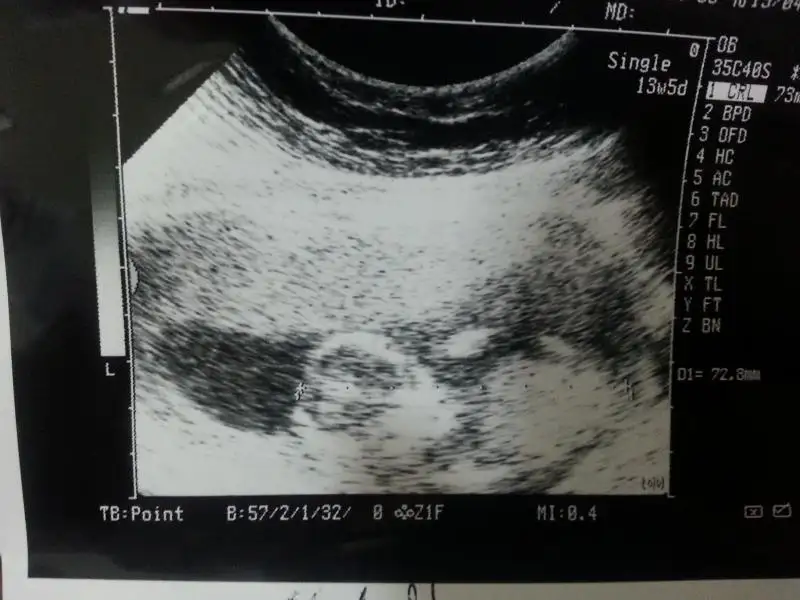

dr soylemeden siz gorun genital nub teorisi ( bebegin cinsiyeti)

$20140624_005921.webp $20140624_005759.webp kızlar bi bakın hele fananay orkide yorum bekliyorum sizdende diğer kızlardanda nolurrrrr:52:

Canım bu benim.oğlumun 12 haftalıkkenki ultrasonu